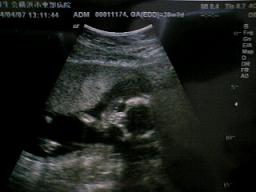

左の写真はわかりにくいので右の写真で図解!

まるでねんねしているかのように、両手を合わせて顔の横に置いてすやすや・・・っていうポーズ!

口はパクパク動いていました^^

先生が「この写真撮っておこうか」と撮影してくれましたw